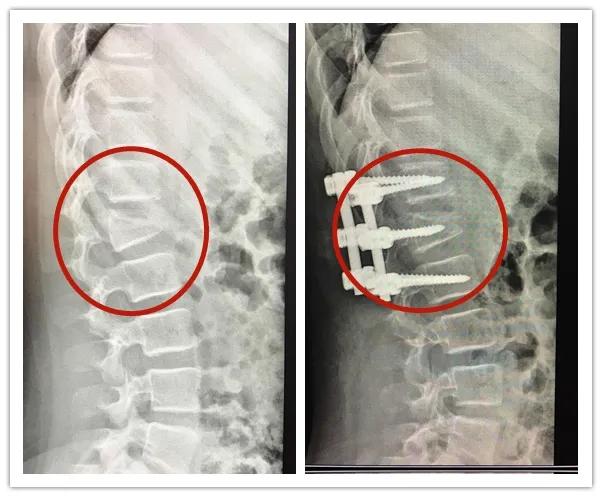

2020年7月,11岁的萱萱在家附近的游乐园玩蹦床,不知道是被其他小朋友撞到,还是自己没站稳,萱萱只记得自己高高弹起后屁股着地摔倒在蹦床上,“很痛。”

经CT检查显示,萱萱第一腰椎椎体爆裂性骨折,且存在明显的后凸畸形。好在手术很顺利,但萱萱需要躺着静养好一段时间,如果要下地行走,需要佩戴好保护支具。

萱萱手术前后